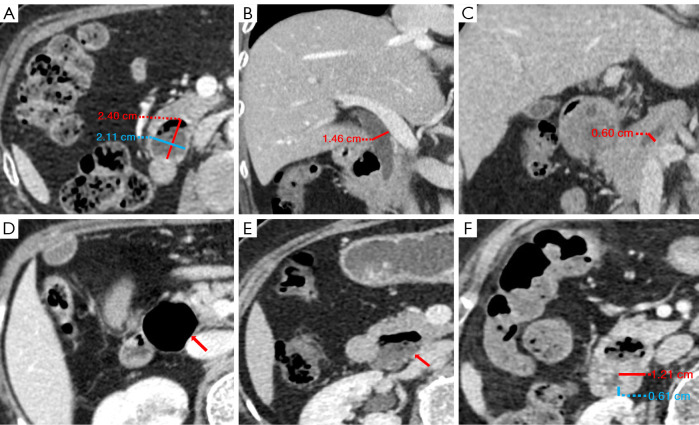

Results: Patients with HRPAD were significantly older than those with N-HRPAD, with an average age of 72±10 and 68±11 years, respectively (P<0.001). Additionally, they exhibited a higher proportion of larger diverticula (>1.95 cm: 65.38% vs. 22.57%), larger common bile duct (CBD) size (>0.69 cm: 72.31% vs. 20.83%), and greater pancreatic duct (PD) dilation (>0.20 cm: 86.92% vs. 60.42%) (all P values <0.001). Furthermore, there was a greater prevalence of diverticular neck swelling in the HRPAD group than in the control group (23.08% vs. 4.86%; P<0.001). Binary logistic regression analysis indicated that a diverticulum size >1.95 cm, CBD size >0.69 cm, PD size >0.20 cm, and the presence of diverticular neck swelling were predictors significantly associated with HRPAD, yielding an area under the curve (AUC) of 0.848; meanwhile, the AUC of the external validation cohort was 0.829.

Conclusions: Patients with HRPAD and those with N-HRPAD exhibited different clinical and imaging characteristics. A thorough understanding of these differences may facilitate early identification of HRPAD and timely treatment interventions, which would reduce complications related to biliary-pancreatic diseases.